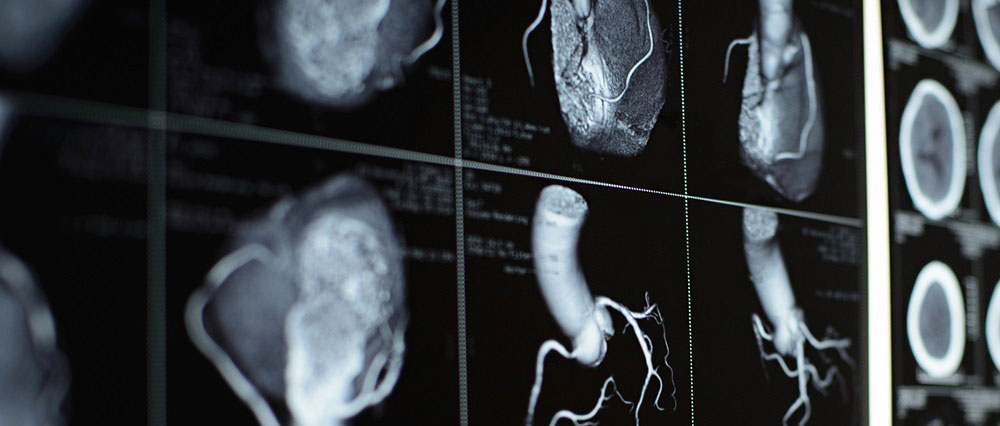

A computerized tomography (CT) coronary angiogram is an imaging test that looks at the arteries that supply blood to the heart. A CT coronary angiogram uses a powerful X-ray machine to produce images of the heart and its blood vessels. The test is used to diagnose a variety of heart conditions.